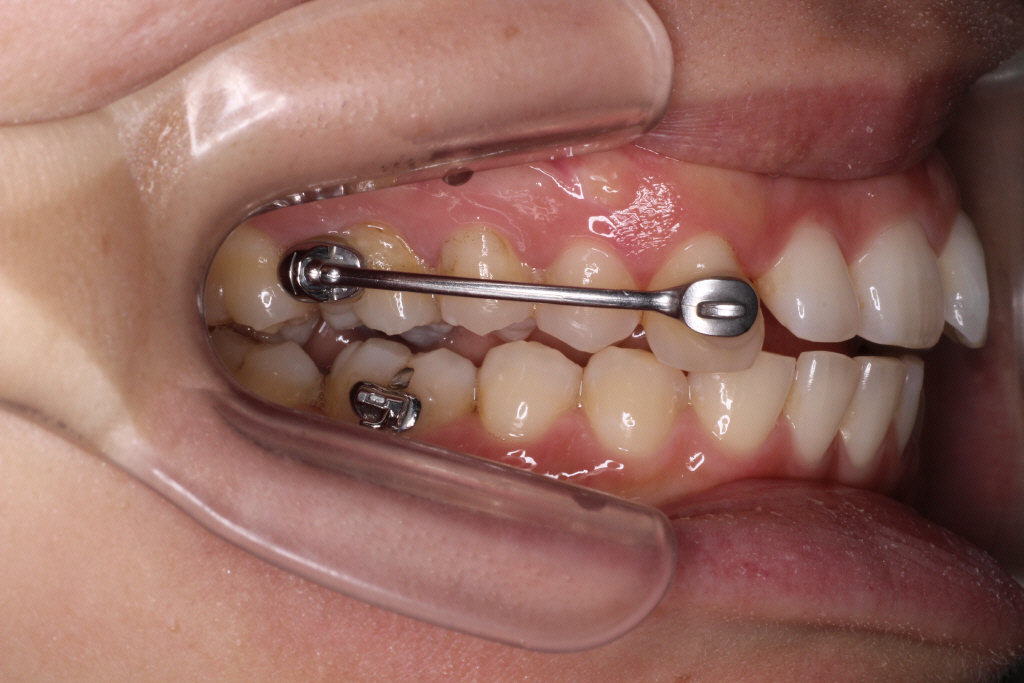

こちらが初診時の口腔内写真です。

上の歯と下の歯の中心がずれています。

また、通常「下の歯2歯に対し上の歯が1歯」というのが正常な歯並びですが

この患者様の場合、右側のみ下の歯が1歯に対し上の歯が1歯になっている事が分かります。

つまり右の咬み合わせは出っ歯の咬み合わせなので上の歯を後ろに下げる必要があります。

診断:上顎前突・上顎前歯部叢生・下顎左側切歯先天欠如